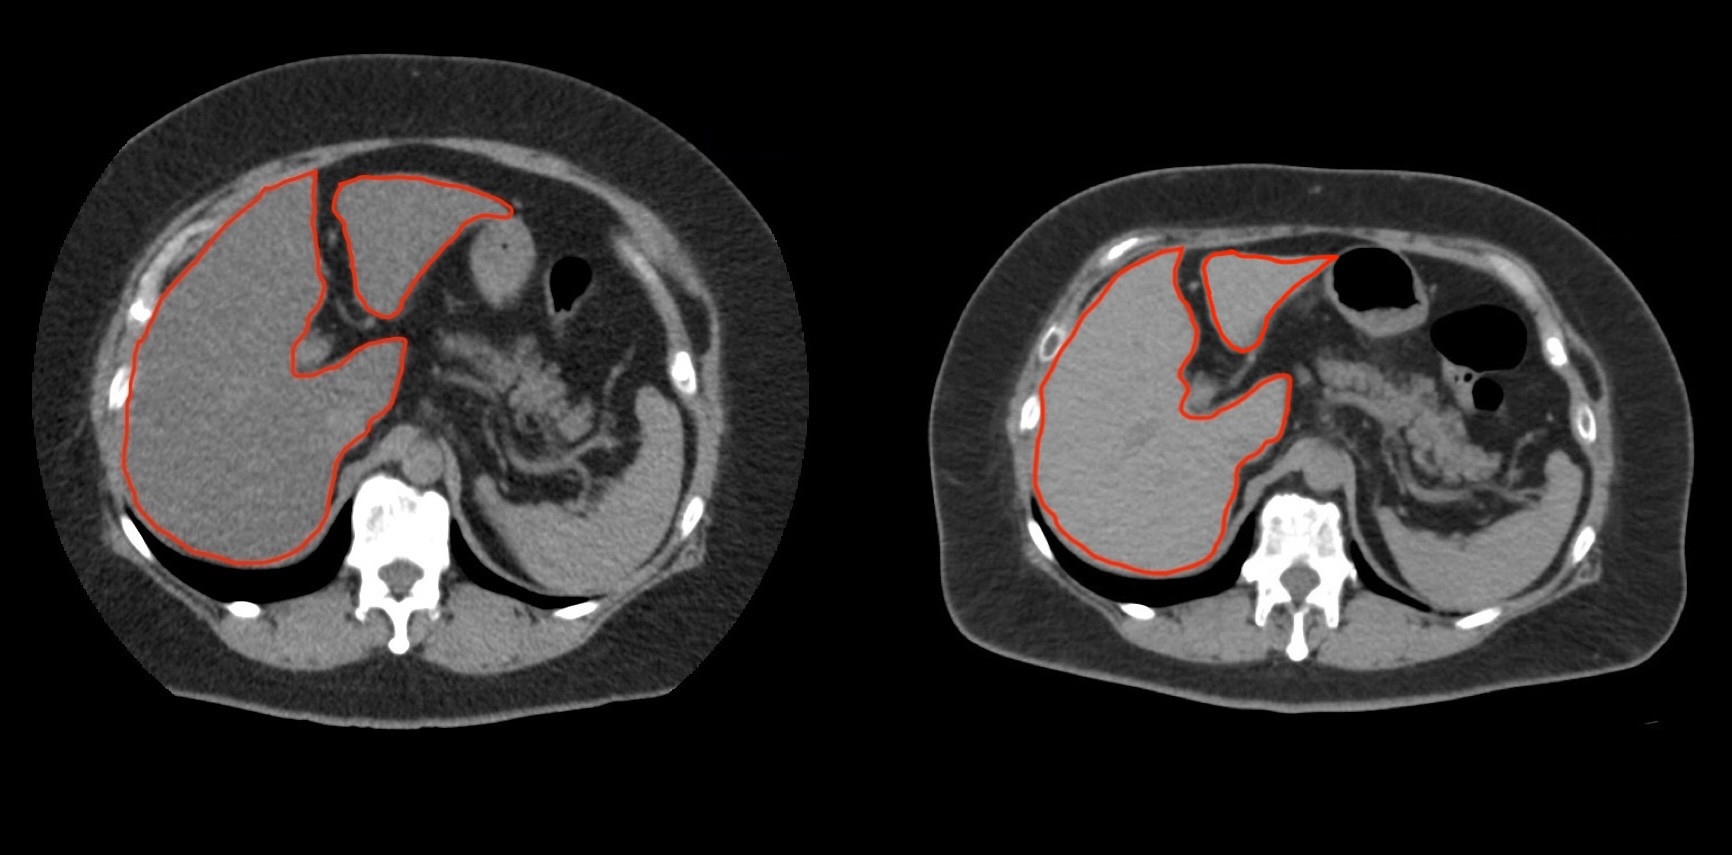

①

50代・女性(ご本人のご厚意で画像提供)

治療内容:チルゼパチド7.5mgの週1回自己注射による脂肪減少と脂肪肝改善

治療期間: 12ヶ月(52週)((用量は2.5mgから開始し最大で15mg。減量効果が得られる必要用量には個人差があります。))

費用:自由診療の場合は9900円(税込)×52(週)=514800円

想定されるリスク・副作用:下記に副作用を記載

※医療広告ガイドラインに準拠して表記

1:脂肪の減少

皮下脂肪の減少(赤色部分)

2:脂肪肝の改善

沈着した脂肪の減少による肝臓の平均CT値の増加(20から50へ)(脾臓の平均CT値は両者とも50)

bluntness of the liver edgeの改善(青色部分)